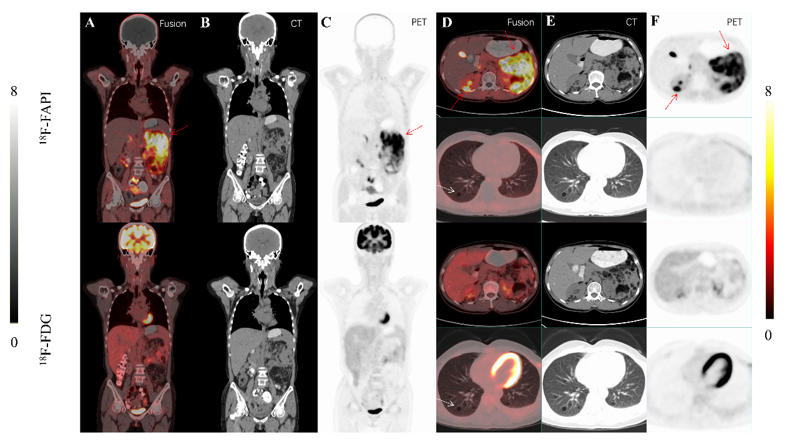

14S-LAM患者(左)和TSC-LAM患者(右)的18F-FAPI-4218F-FDG的最大强度投影(MIP)图像对比情况。在18F-FAPI-42图像中,腹膜后区域(邻近腹主动脉和双侧髂动脉)、骨盆以及部分患者的纵隔和双侧腹股沟区域观察到不同程度的高代谢病灶,而这些病灶在18F-FDG成像中未见显著摄取。在TSC-LAM患者中,观察到不同程度的肾血管平滑肌脂肪瘤,其在18F-FAPI-42成像中显示出显著的放射性示踪剂摄取,而在18F-FDG成像中未见明显摄取。此外,LAM患者的肺囊性病变在18F-FDG18F-FAPI-42成像中均未见显著放射性示踪剂摄取。图中黑色箭头指示淋巴管平滑肌瘤,红色箭头指示肾血管平滑肌脂肪瘤,(黑箭:淋巴肌瘤;红箭:RAML)。

图片

2一名26岁典型S-LAM女性患者的18F-FDG18F-FAPI-42成像情况。18F-FAPI-42显像显示腹主动脉、双侧髂血管及双侧腹股沟区域存在结节样及线样高代谢病灶(箭头所示),而18F-FDG成像在这些区域未检测到显著摄取。